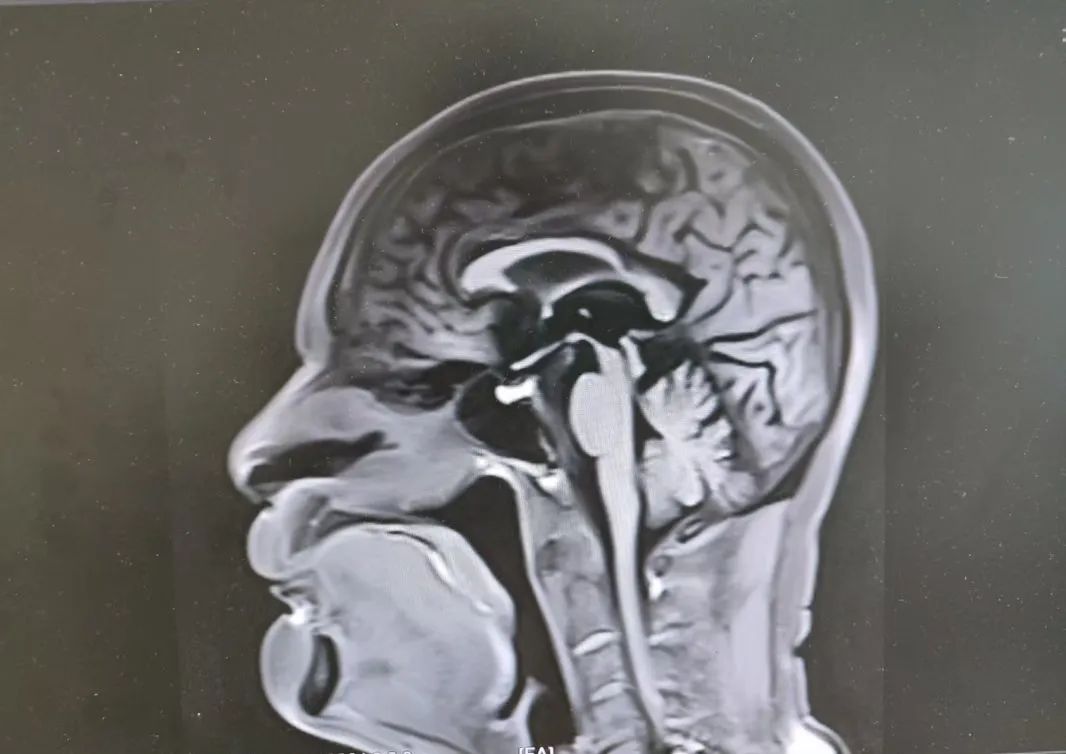

81歲的李大爺(化名),一年前開(kāi)始右側(cè)肢體不靈,走路向后傾斜,期間經(jīng)常跌倒,隨著癥狀逐漸加重,家屬趕緊帶著老人找到趙智江教授。入院后,趙智江教授發(fā)現(xiàn)患者存在肌張力增高、運(yùn)動(dòng)遲緩、站立時(shí)向后傾倒、眼球垂直運(yùn)動(dòng)障礙等癥狀,腦部核磁發(fā)現(xiàn)特征性“蜂鳥(niǎo)征”圖像,結(jié)合相關(guān)血液檢驗(yàn)結(jié)果,排除帕金森綜合征和僵人綜合征等干擾,確診為進(jìn)行性核上性麻痹(PSP)。

患者核磁“蜂鳥(niǎo)征”影像

進(jìn)行性核上性麻痹是帕金森疊加綜合征之一,多發(fā)于中老年人,容易被忽視或誤診為帕金森病。此次明確診斷,為李大爺?shù)闹委熤该髁朔较?,?duì)提高李大爺?shù)纳钯|(zhì)量起到了重要作用。